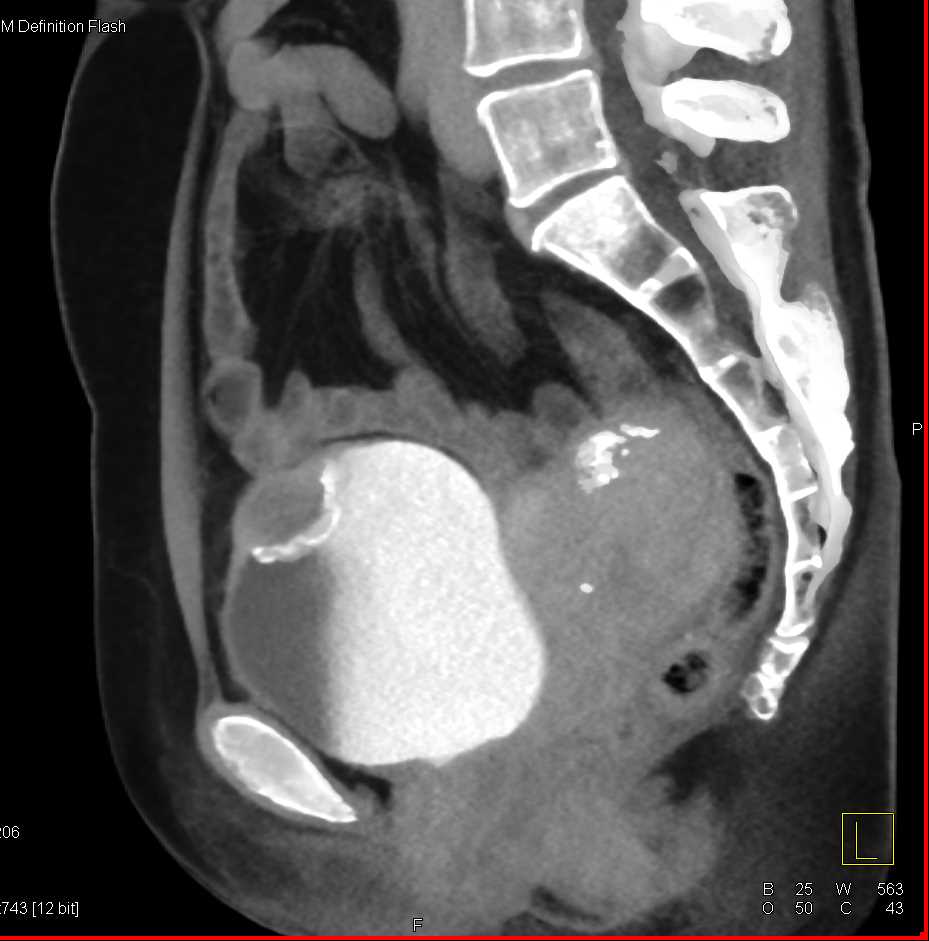

Urachal Carcinoma of the Bladder